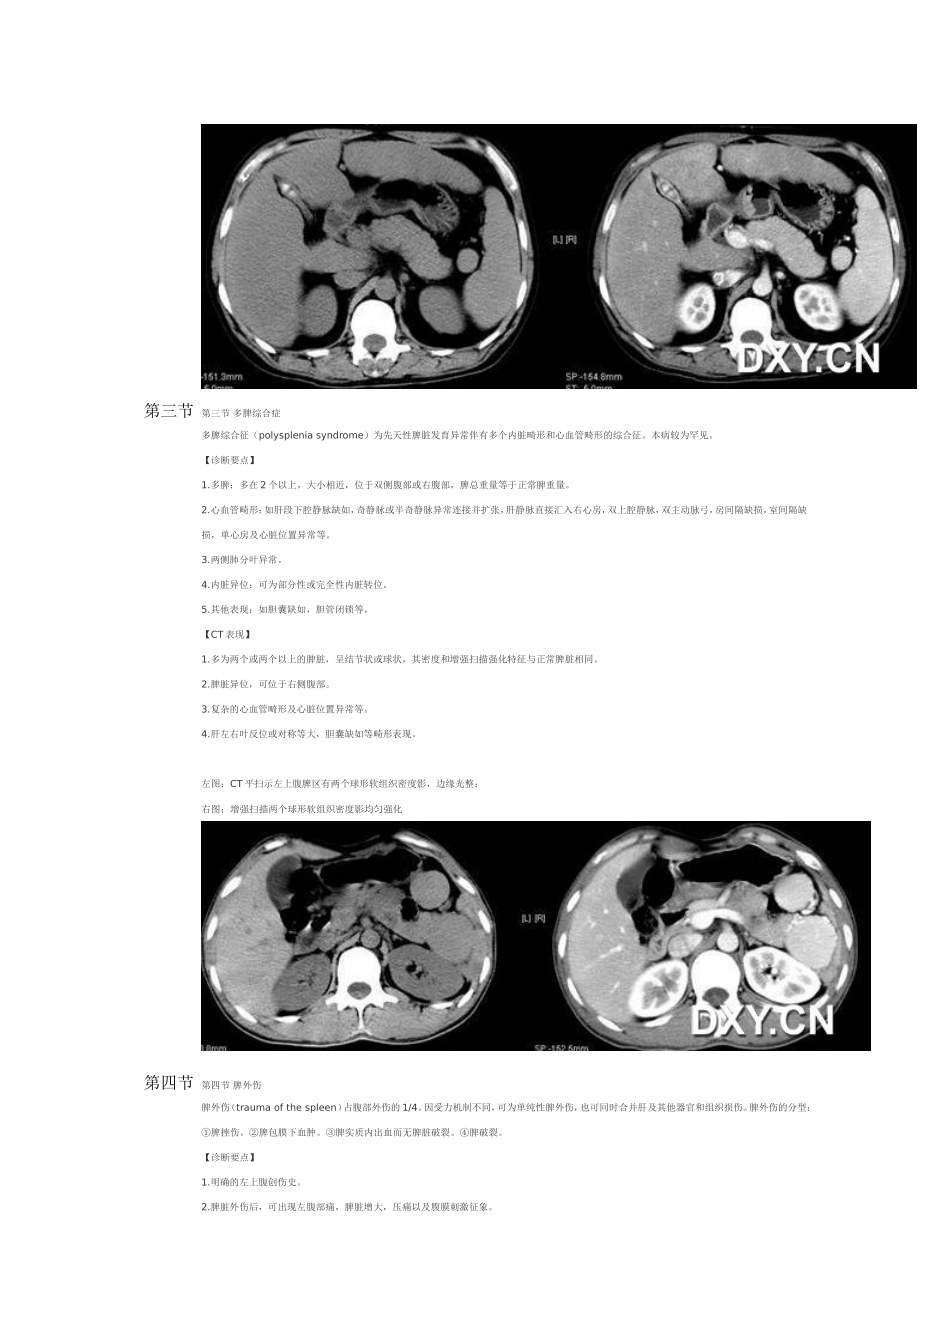

第一节脾肿大脾脏弥漫性疾病多表现为脾肿大(enlargedspleen)。脾脏大小个体差异较大,解剖学测量脾脏的平均长10.5cm,宽6.5cm,厚2.5cm,最大径超过15cm者肯定增大。引起脾肿大的病因很多,主要有炎症性、淤血性、增殖性、寄生虫感染、胶原病和浸润性病变等。诊断要点:1.症状和体征:1)部分患者无明显自觉症状。2)脾肿大病因不同而致临床症状各异。3)深吸气时,脾脏触诊在肋缘下超过2~3cm。叩诊时,脾浊音区相应扩大。2.X线平片:脾脏X线测量长径超过15cm,宽径超过8cm可诊断脾肿大。明显增大时可引起左膈升高,胃泡右移,左肾轮廓影向内下方移位。3.消化道钡餐造影:可显示脾大对胃肠道的压迫、推移征象,结肠脾曲下移,相应的横结肠上缘出现压迫。4.MRI检查:单纯性脾肿大MRI信号强度均匀。【CT表现】1.CT平扫:显示弥漫性脾肿大的程度、形态、实质密度变化及周围组织和器官的压迫推移征象。1)长径超过10cm,短径超过6cm,上下方向长度超过15cm即为脾肿大(图6-5-1A)。2)横断面图像上以5个肋单元作为标准,超过者为脾肿大。若肝下缘消失的层面上,脾下缘仍能见到则可认为脾向下增大(图6-5-1B)。3)当脾脏密度高于肝脏密度时,提示有肝脏弥漫性病变。2.增强扫描:动脉期脾脏呈斑片状不均匀强化,静脉期及平衡期强化密度逐渐均匀。弥漫性脾肿大超过5个肋单元第二节第二节副脾副脾(accessoryspleen)又称额外脾。为先天性异位脾组织,与主脾结构相似,具有一定功能的脾组织。约占尸检10%~30%,多为单发,常位于脾门或沿脾血管分布,也可沿脾脏的悬韧带分布。约有20%的副脾发生在腹部或后腹膜的任何地方。【诊断要点】1.症状与体征:通常无临床症状,较大者可于上腹部触及肿块。2.消化道钡餐造影:位于胃壁或胃周围者,可显示类似胃粘膜下肿瘤征象。3.MRI检查:形态上呈圆形或椭圆形,信号特征与主脾相同,增强扫描,副脾与主脾的强化一致。4.DSA检查:可见脾动脉的小分支进入副脾,与主脾染色一致。【CT表现】1.CT平扫脾门部小结节,多数直径不超过2.5cm,边缘光滑。偶见位于脾门以外者。2.增强扫描副脾与主脾强化一致,CT值相同。3.动态增强扫描:两者的增强与消退之动态变化也完全一致。4.鉴别诊断:需与腹部肿瘤鉴别,勿把副脾误认为淋巴结肿大或其他肿物。脾摘除后副脾可增大。副脾也可发生脾脏的病变,如淋巴瘤。左图:CT平扫示脾门处类圆形小结节影,边界光滑右图:增强扫描脾门部小结节影均匀强化,与脾脏强化一致第三节第三节多脾综合症多脾综合征(polyspleniasyndrome)为先天性脾脏发育异常伴有多个内脏畸形和心血管畸形的综合征。本病较为罕见。【诊断要点】1.多脾:多在2个以上,大小相近,位于双侧腹部或右腹部,脾总重量等于正常脾重量。2.心血管畸形:如肝段下腔静脉缺如,奇静脉或半奇静脉异常连接并扩张,肝静脉直接汇入右心房,双上腔静脉,双主动脉弓,房间隔缺损,室间隔缺损,单心房及心脏位置异常等。3.两侧肺分叶异常。4.内脏异位:可为部分性或完全性内脏转位。5.其他表现:如胆囊缺如,胆管闭锁等。【CT表现】1.多为两个或两个以上的脾脏,呈结节状或球状,其密度和增强扫描强化特征与正常脾脏相同。2.脾脏异位,可位于右侧腹部。3.复杂的心血管畸形及心脏位置异常等。4.肝左右叶反位或对称等大,胆囊缺如等畸形表现。左图:CT平扫示左上腹脾区有两个球形软组织密度影,边缘光整;右图:增强扫描两个球形软组织密度影均匀强化第四节第四节脾外伤脾外伤(traumaofthespleen)占腹部外伤的1/4。因受力机制不同,可为单纯性脾外伤,也可同时合并肝及其他器官和组织损伤。脾外伤的分型:①脾挫伤。②脾包膜下血肿。③脾实质内出血而无脾脏破裂。④脾破裂。【诊断要点】1.明确的左上腹创伤史。2.脾脏外伤后,可出现左腹部痛,脾脏增大,压痛以及腹膜刺激征象。3.当伴有脾破裂时,血压下降,血红蛋白急速下降,并有休克等严重症状。4.X线平片:脾脏形态变化,破裂出血时轮廓不清或消失,反射性肠郁张,合并肋骨骨折,胸腹腔积液等征象。5.腹腔动脉造影:可见对比剂外溢,动脉闭塞,动静脉瘘,假性动脉瘤形成,无血管区和包膜下血肿及脾周围腹腔内血...